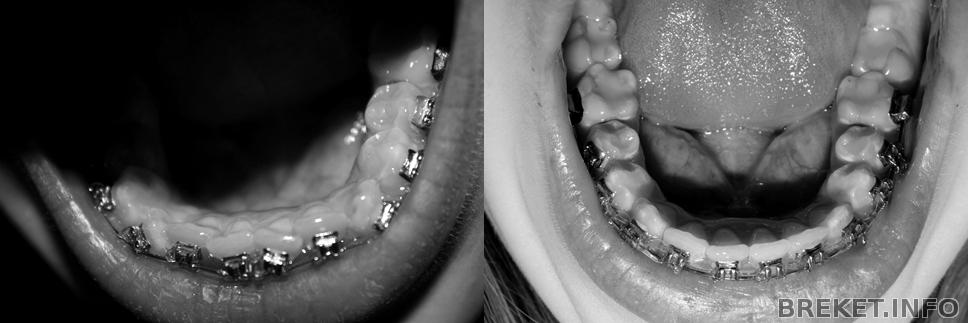

Давно я тут не отмечалась, хотя на сайт заглядываю частенько. А между тем, время идет...уже 2 года, как я в брекетах. Прогресса уже такого заметного, как в начале, нет, все двигается ооочень медленно. О снятии речи пока нет, сейчас двигаем единичку на ВЧ. А сегодня сделала фотки, посмотрела на НЧ, ужас, центр реально сдвинулся в одну сторону на целый зуб(. Сделала коллаж, смотрите.

1д.1г.2г.ВЧ